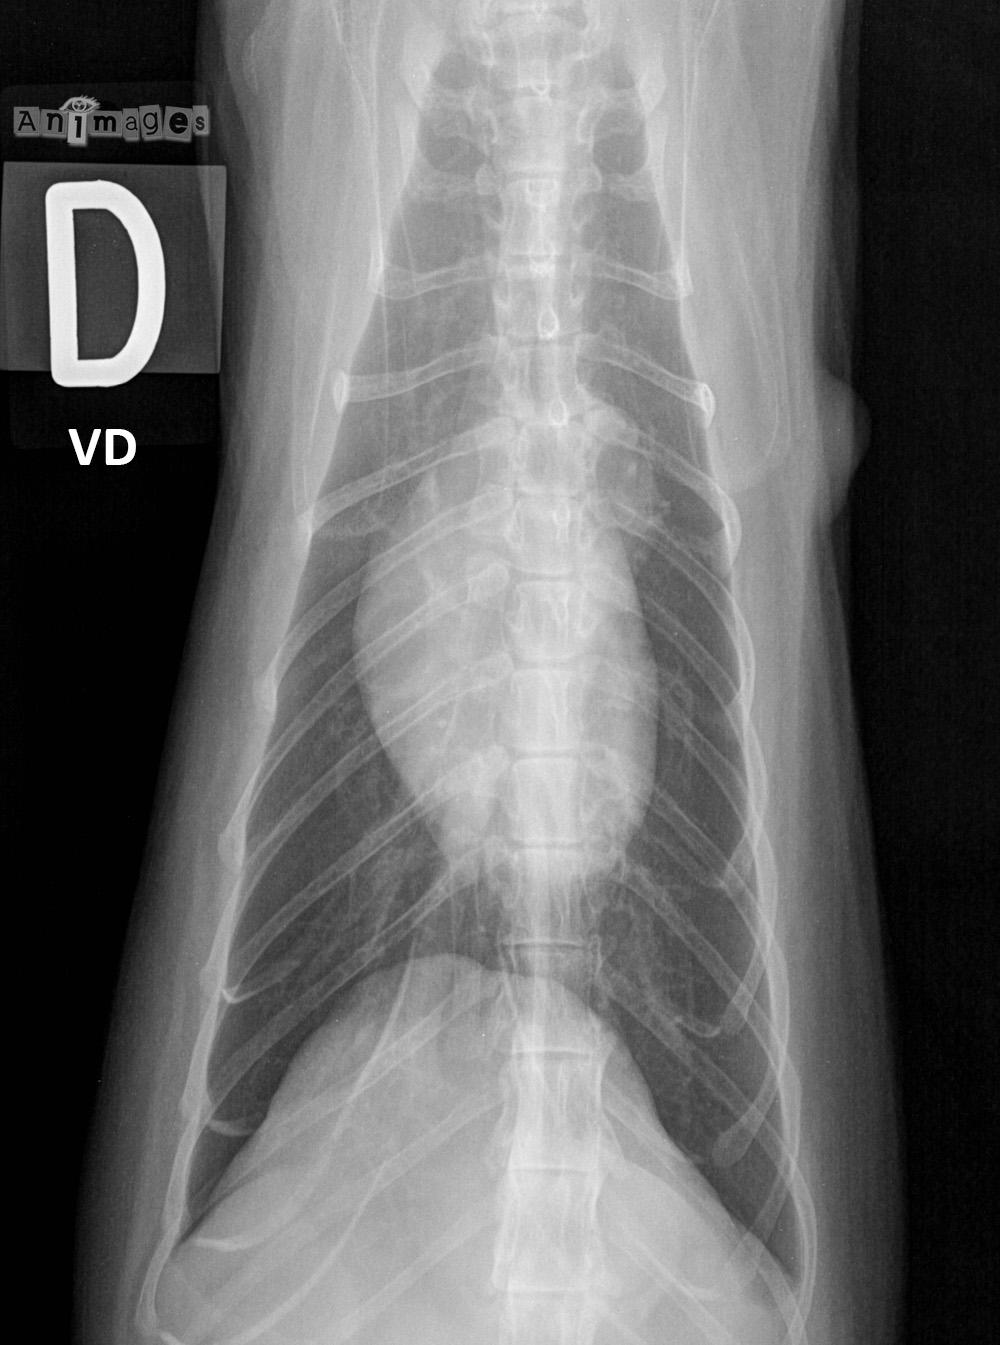

- Publié 13 février 2013 à 1000 × 1345 dans Docteur, c’est quoi cette tache blanche sur le coeur de mon chat ?

a/n peau, masse? a/n coté gauche derriere l’epaule.